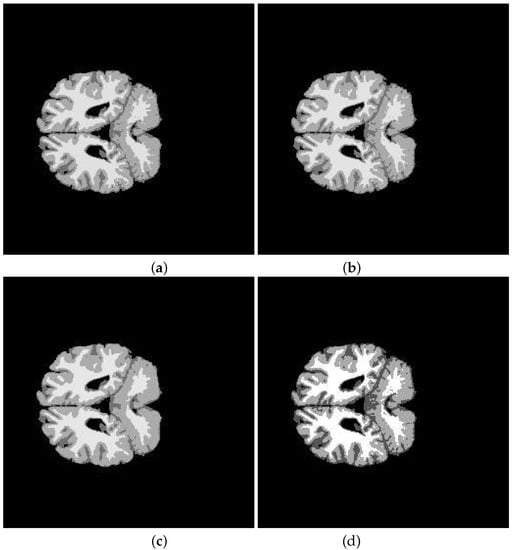

- by the cluster centroid color: Each point of a cluster is labeled with the color of its centroid (in the case of color conversion, the color space is converted back to RGB);

- by a gray level: Each pixel is labeled with the number of the cluster it belongs to, and the range is stretched in 0–255;

- by a random RGB color: A random RGB value is generated for each cluster;

- by a binary stack: The clustering is represented as a stack of binary images. Each binary image represents a cluster; each pixel shows a hard cluster membership. Thus, it is possible to extract cluster regions from the original image by performing an AND operation between a slide of the stack and the original image.

- by using a fuzzy stack: A stack of gray level images is used to show the membership values of each pixel to each cluster. Each pixel represents the soft cluster membership value of that pixel in the original image according to the currently selected cluster.